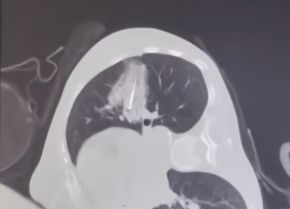

▲2024年9月术前影像报告

于是,王阿姨再次回到广州复大肿瘤医院就诊,检查提示左肺有多个磨玻璃结节影,较大者约1.3x1.1cm。考虑到王阿姨心脏的问题且拒绝手术切除,在排除各项禁忌后,牛立志院长为其施行左上肺结节冷冻消融术。

▲术中冷冻针直击肺结节中心